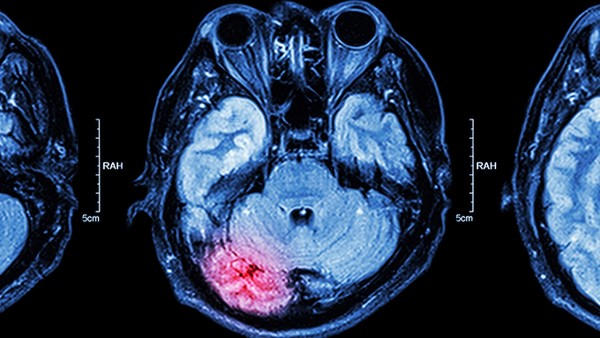

在日常生活中,中风是众所周知的疾病,脑出血是中风的一种,死亡率达到30%~40%,主要是由长期高血压、高脂血症等因素引起的,感情兴奋,用力过猛,可能引起脑出血,引起一系列后遗症那么,如何预防脑出血呢?